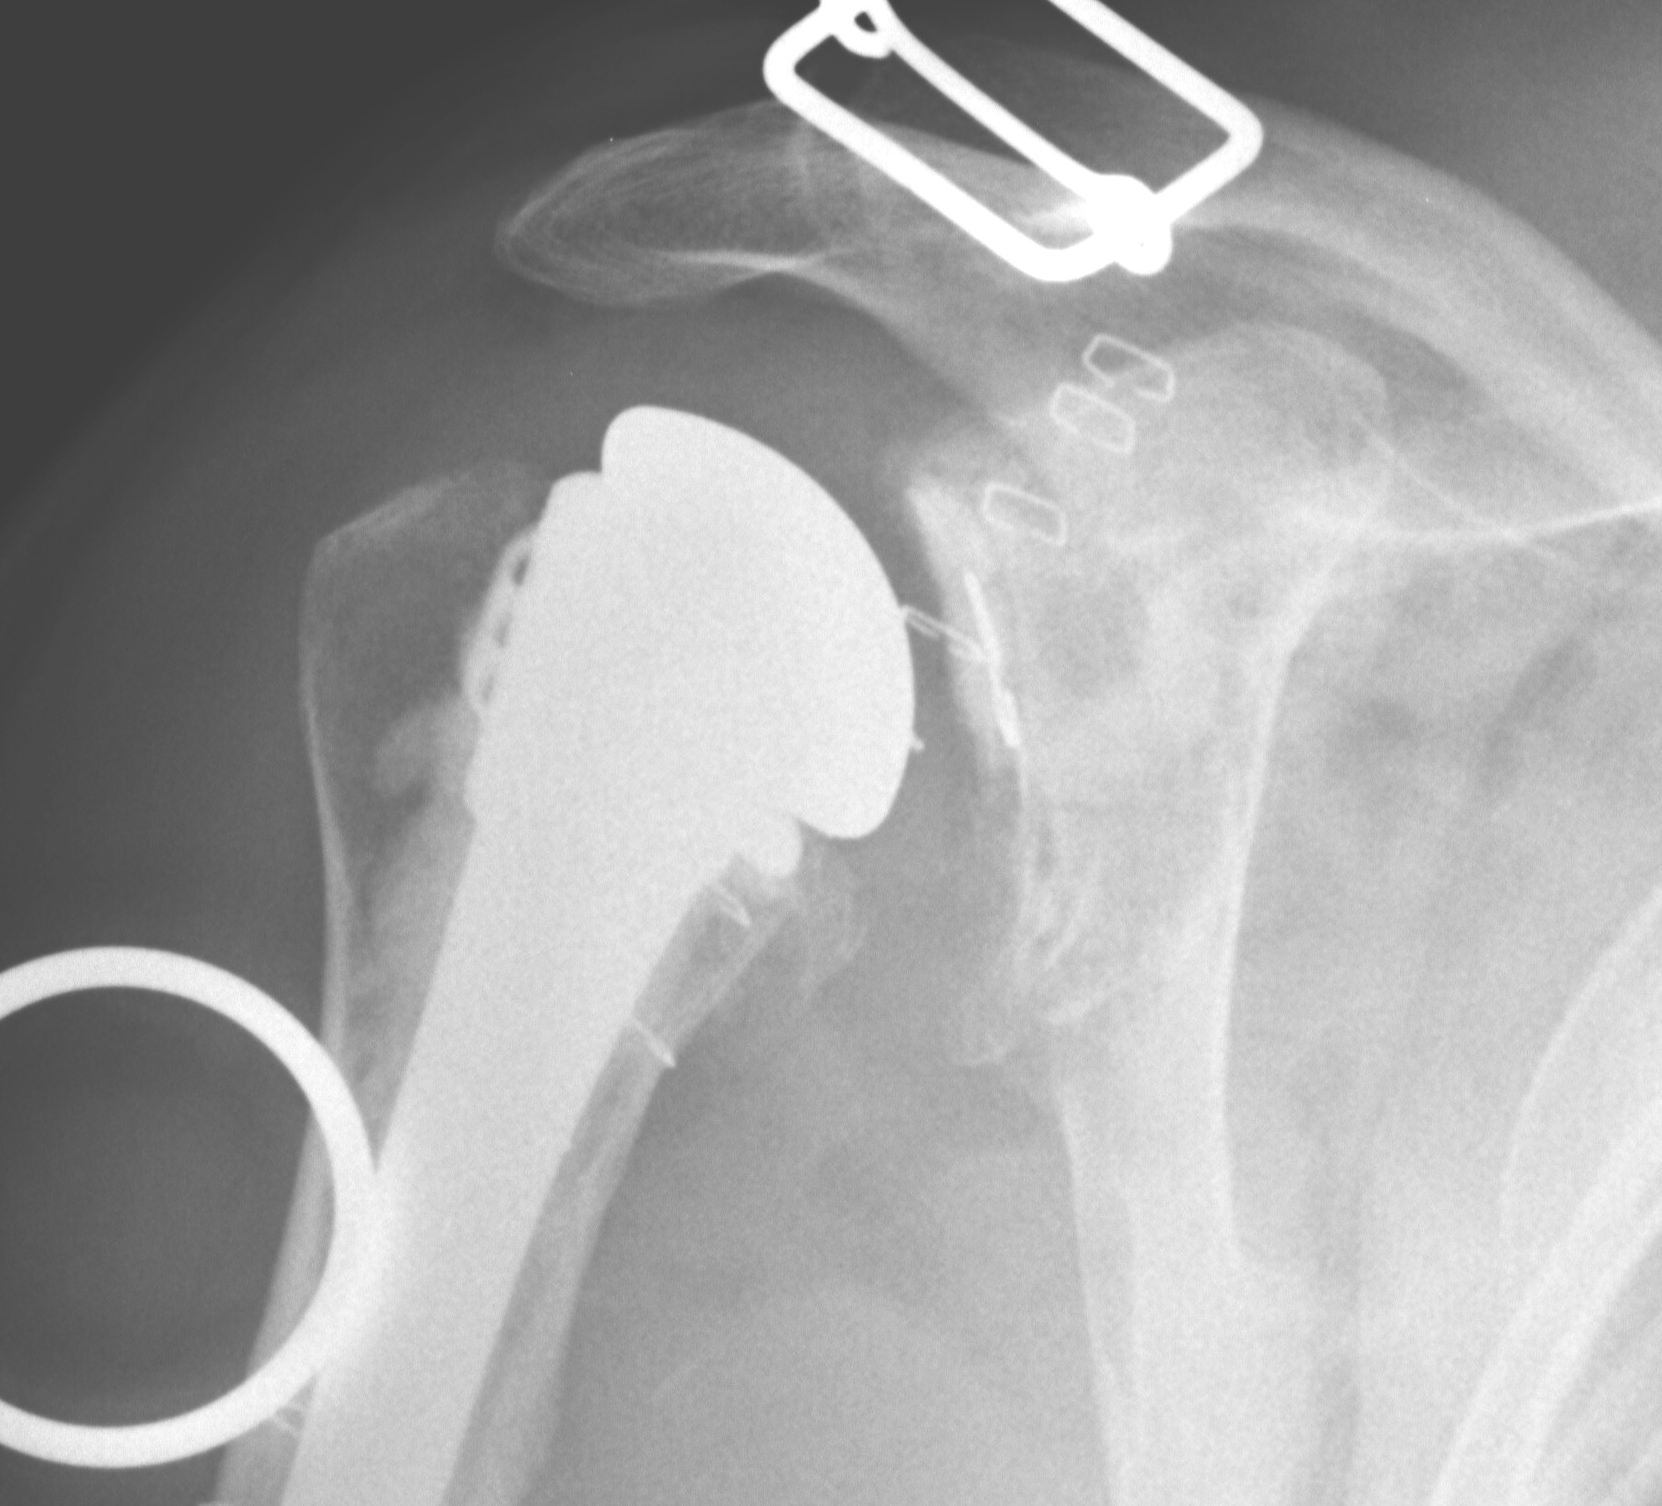

Revision Humeral Component

Technique

- often need long stem

- often use cement in revision circumstance